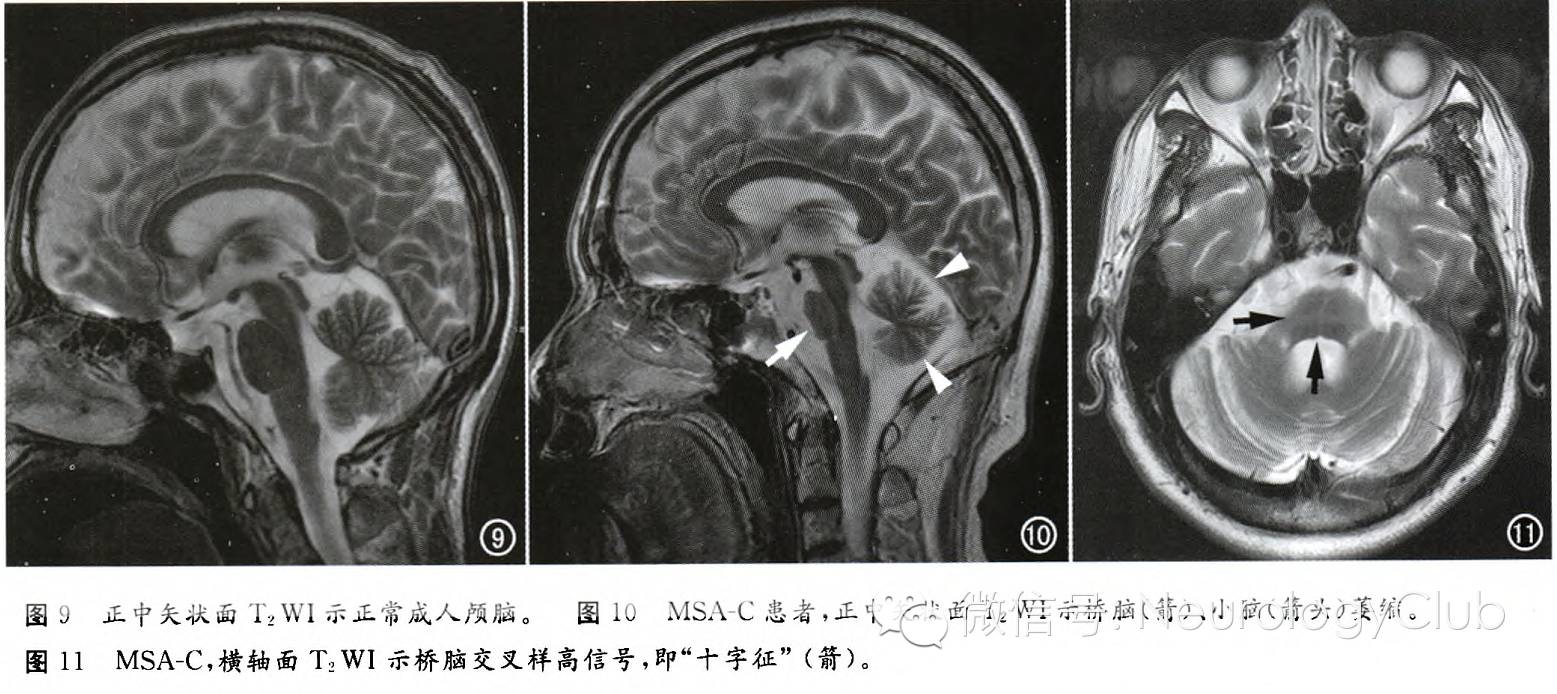

十字面包征(简称“十字征”,Hot cross bun sign)

MSA-C的MRI影像学表现包括橄榄、桥脑、小脑中脚和小脑的萎缩,横轴面上桥脑T2WI交叉样高信号,即所谓的“十字征”,是诊断MSA-C的较特征性的表现。“十字征”的病理学基础为桥脑核及其发出的通过小脑中脚到达小脑的纤维(桥横纤维)变性和神经胶质增生,T2WI信号增高,而锥体束和由齿状核发出的小脑上脚的纤维无变性,未出现异常信号。有学者认为,先出现“垂线征”,后出现“十字征”。“十字征”形成过程与桥脑小脑萎缩程度之间存在相关性,当“十字征”等级越高时,对应其桥脑面积越小。因此,根据MRI图像诊断MSA-C的敏感性和特异性非常高。然而,在脊髓小脑共济失调其他类型如SCA1、SCA2、SCA3以及继发于某种血管炎的帕金森征合并小脑、脑干功能障碍患者中,有相同的MRI影像学特点和组织学特点。

(脑桥“十字征”伴小脑萎缩